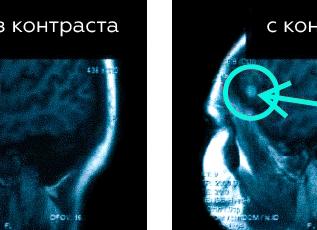

Эта диагностика с красящим средством помогает выявить увеличение или уменьшение органов, их повреждения и отсутствие. Пораженные ткани имеют свойство под воздействием красящего препарата изменять цвет, что позволяет определить границы той или иной патологии.

Снимок головного мозга после МРТ с контрастом

К примеру, при опухоли. МРТ с контрастированием помогает выявить мелкие метастазы, которые при обычном исследовании не заметны. Контраст же дает возможность четко определить размеры образование и правильно спланировать оперативное вмешательство. А также определить возможные рецидивы после операции, установить, уменьшилась ли опухоль после проведенного лечения.